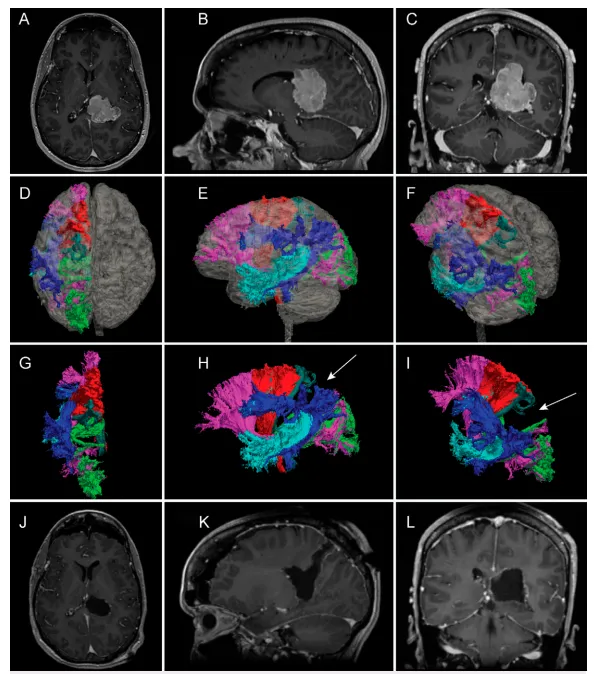

磁共振成像检查结果显示一处强化的脑室内占位性病变。图1A-C为钆增强T1加权磁共振图像,清晰显示位于左侧侧脑室前角区边界清楚、明显强化的病灶。影响此类病变手术入路选择的因素众多,特别是该区域周围的白质通路分布。术前弥散张量成像可对该区域白质纤维束进行细致评估。图1D-I呈现该区域弥散张量白质纤维重建结果。虽然处理侧脑室前角区病变已有经颞叶入路的文献描述,但图1中的重建图像显示密集的弓状束和上纵束阻挡了经颞叶的手术通道。图1J-L底部区域为术后磁共振图像,显示通过中线旁经顶叶手术入路实现的肿瘤全切。

A–C:术前T1加权钆增强磁共振成像显示优势半球脑室内脑膜瘤的轴位、矢状位及冠状位图像。

D–I:弥散张量纤维束成像三维重建的主要白质纤维束。图D、E、F分别为叠加患者磁共振透明重建模型后的上视图、左侧视图及左上前斜视图。图G、H、I为不叠加磁共振脑图像时相同视角下的白质纤维束显示。各纤维束颜色标示如下:额枕下束呈粉红色;运动束呈红色;感觉束呈深绿色;视辐射呈黄绿色;上纵束呈深蓝色;弓状束呈浅蓝色。

J–L:显示患者经中线旁经顶叶入路实现全切后的术后磁共振影像。

经顶叶入路提供了避开重要白质纤维束的手术机会。先前研究文献描述的经顶叶入路多采用斜行轨迹。如图1D-I所示,经皮质、经顶叶的中线旁通道在前方以感觉束为界,后方以视辐射为界,下方以额枕束为界,外侧以上纵束和弓状束为界。图1中内侧区域无明显的重要白质纤维束分布,这表明从功能保护角度分析,中线旁轨迹可能属于最安全的手术路径。